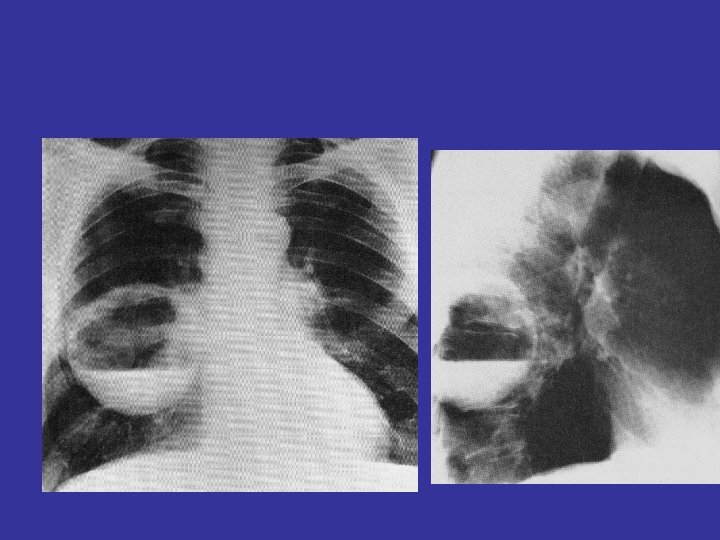

lateral view ? ! can detect otherwise hidden masses

The lateral chest film our best friend • Find abnormalities on the frontal film

The lateral chest film our best friend • Find abnormalities on the frontal film • Confirm abnormalities suspected from frontal film • Don’t be afraid to look at it